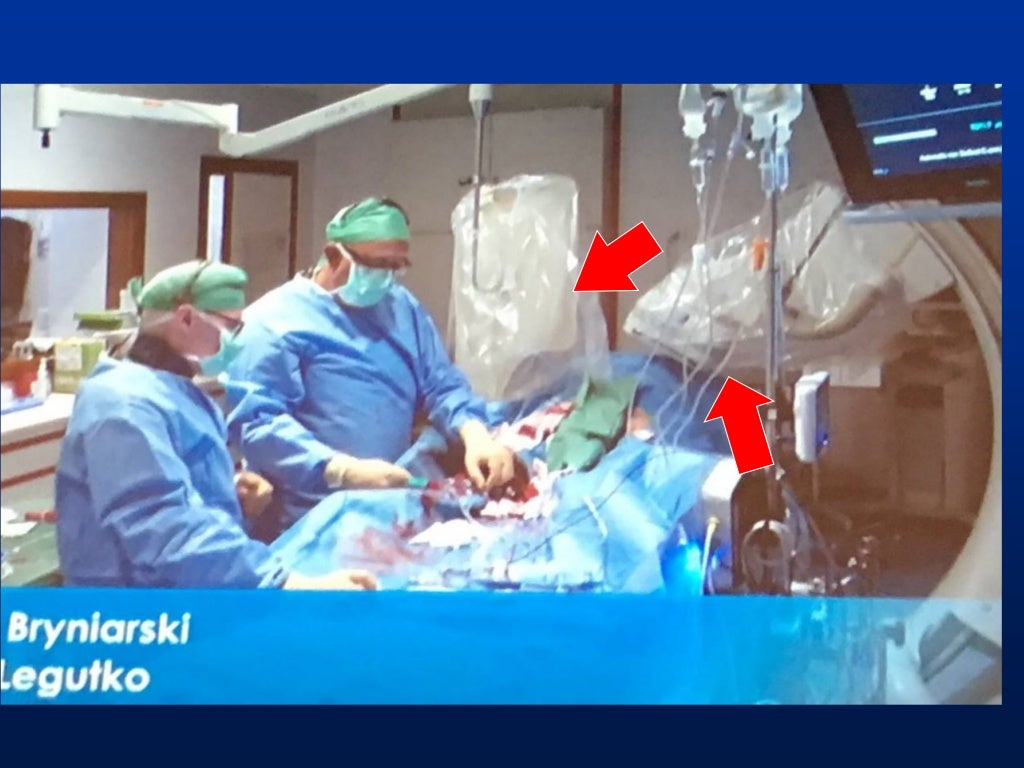

I) use collimator to set minimal useful field size, keep image intensifier in close proximity.

There are various types of shielding used in the reduction of radiation exposure including lead aprons, mobile lead shields, lead glasses, and lead barriers. The purpose of this article is to (a) describe the importance of educating radiology personnel, patients, and referring clinicians about the concerns over ct radiation, (b). Every diagnostic medical procedure involving ionizing radiation needs to minimize radiation exposure without compromising the benefit for the patient.

Steps we take to minimize radiation. Time, distance, and shielding measures minimize your exposure to radiation in much the same way as they would to protect you against overexposure to. Time, distance, and shielding actions minimize your exposure to radiation in much the same way as they would to protect you against overexposure to the sun: